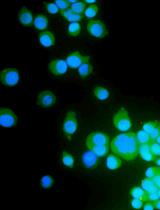

We previously used ginger-derived lipid nanoparticles (GDNPs) for orally delivering CD98 siRNA (Zhang et al., 2017) and 6-shogaol (Yang et al., 2021) to treat ulcerative colitis. These studies suggested that GDNPs could overcome the challenges of oral drug delivery. Further, we found that monogalactosyl-diacylglycerol (MGDG), digalactosyl-diacylglycerol (DGDG), and phosphatidic acid (PA) constitute more than 90% of the total lipids of GDNPs (Zhang et al., 2016; Zhang et al., 2017). In this protocol, we will describe how to use these three lipids at the same ratios found in the GDNPs in the synthesis of new lipid nanoparticles (nLNPs) to encapsulate IL-22 mRNA. The nLNP-encapsulated mRNA showed its therapeutic efficacy in one of our recently published studies (Sung et al., 2022).